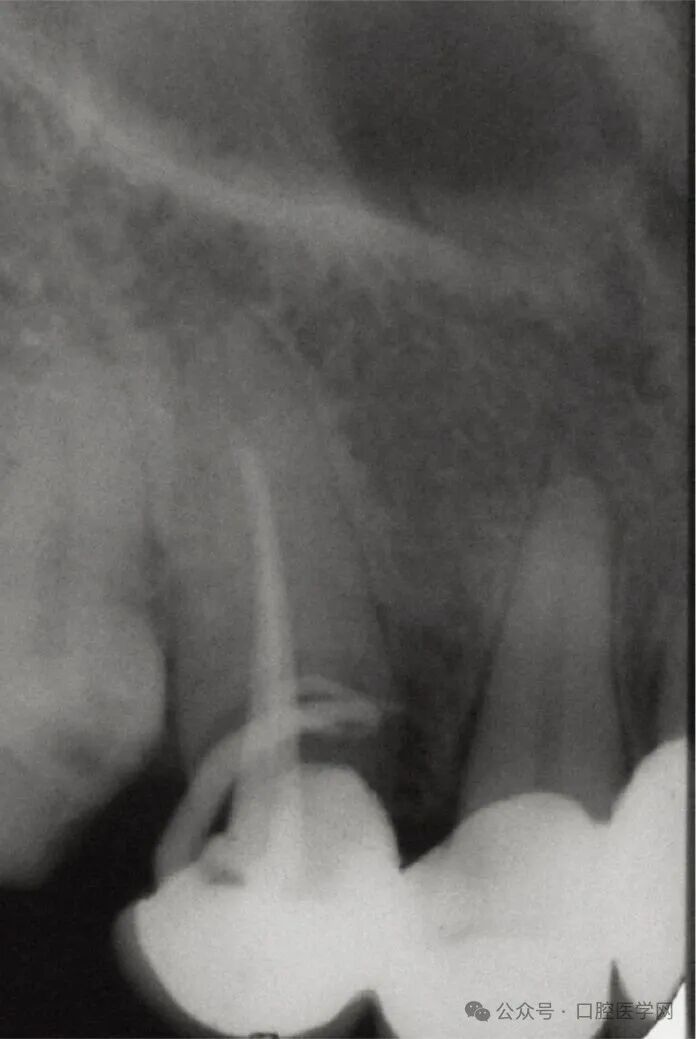

常规根尖片显示右上尖牙根管充填不完全,根尖区有大范围的透射影,牙周韧带间隙消失,硬骨板增宽,如图3所示。但常规片无法明确充填材料是位于根管内还是根管外,也不能准确判断哪颗牙齿是症状的真正来源。CBCT检查证实牙周韧带间隙内存在与根管相邻的不透射充填材料,而根管本身呈空虚状态,如图4和图5所示。尖牙根尖以外未发现被挤压出的充填材料。

图3 口内术前放射片显示13号牙根管充填不充分,根尖区有大面积透射影。